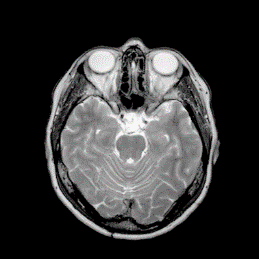

Where x is denoted as the MRI to be reconstructed, y are the k-space data, and Fusubscript𝐹𝑢{F_{u}} represents the under-sampled Fourier encoding matrix. The first term Fuxy22superscriptsubscriptnormsubscript𝐹𝑢xy22{\|{F_{u}}\emph{x}-\emph{y}\|}_{2}^{2} indicates data fidelity that can ensure the consistence between the Fourier coefficients of the reconstructed image and measured data. The second term Risubscript𝑅𝑖{R_{i}} is an analytical, sparsifying transform term, and αisubscript𝛼𝑖{\alpha_{i}} is a factor for balancing data fidelity and transform terms. MR images can be generated by inverse Fourier transform of the sampled k-space data, which are the Fourier coefficient of an object. However, aliasing artifacts (noise-like) are produced by the incoherence of under-sampled k-space in transform domain, as shown in Fig. 1.

Figure 1: The zero-filled reconstruction. (a) is a full-sampled MRI, (b) is a 20% radial sampling mask, (c) is the zero-filled reconstruction under (b), and (d) is the reconstruction using our method. Note that aliasing artifacts are clearly seen in the zero-filled reconstruction (c), which impair diagnostic information. However, our algorithm can remove these unpleasant artifacts (d).